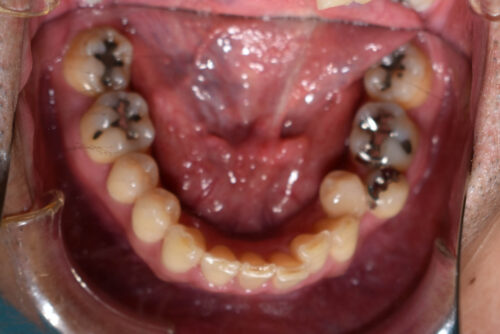

初診時年齢 46歳 男性

歯のでこぼこ(叢生)

左下第二小臼歯が 外に飛び出している

と

頬側転位

を主訴に

かみ合わせが深く

がたついている 状態でした。

ワイヤー矯正治療12か月後です。